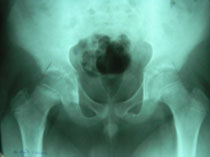

What is perthes disease?

Perthes disease is a disease of the hip in which the bone in the hip joint loses its blood supply. This may cause the bone (femur) to change shape so that it no longer fits into the hip joint (femoral head) properly. The disease run a 2-year course, and if left untreated, can cause permanent damage to the bone.

The first stages of perthes disease are silent. This means that the patient dose not limp or complain of pain. The bone in the hip joint (top of the thigh bone or femoral head) loses its blood supply and that part of bone subsequently dies. The bone weakens and a small fracture develops, with the result that the femur head begins to flatten. Circulation returns to the head of the femur within months, rejuvenating the bone but causing pain and a limp (and a visit to the doctor). If left untreated, the femoral head may flatten over the course of months. Leading to arthritis in later years.

Because many disease processes have signs and symptoms similar to those of perthes disease, it is diagnosed by x-rays. The first x-ray may not be helpful. Because characteristic signs may not have appeared. Bone scans and magnetic resonance images (MRI’s) can be used to detect the amount of blood circulation in the femoral head.

A two-group classification for perthes has been developed. Group A consists hips with less than half of the femoral head involved. This group generally needs little treatment and recovers well. Group B includes hips with more than half of the femoral head involved. Patients in this group need treatment to do well.